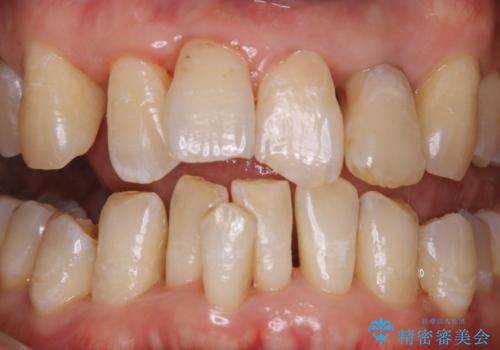

歯周病の治療前にまずはモチベーションUPにPMTCでステインの除去

担当医 歯科衛生士